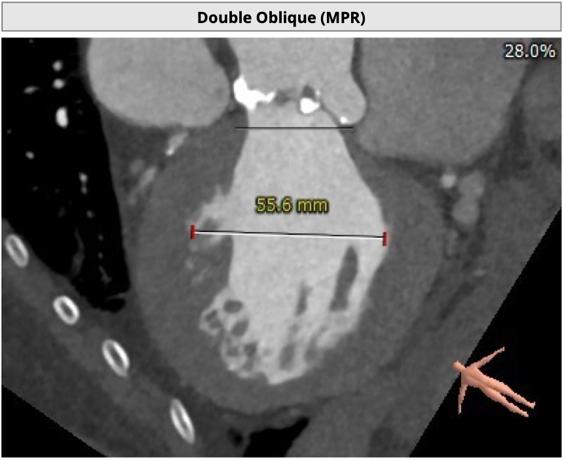

CT 数据显示该患者为Type1型二叶式主动脉瓣

主动脉瓣瓣环周长76.8mm,周长径24.5mm;

LVOT 周长 86.1mm,周长径27.4mm;

SOV:32.3mm*34.5mm*33.7mm;

STJ 周长 100.6mm;

瓣叶严重粘连增厚,瓣叶钙化明显,HU850:1448.3mm³。